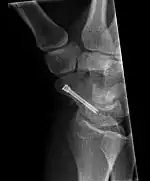

Scaphoid fracture before and after operation

The scaphoid can be slow to heal because of the limited circulation to the bone. Fractures of the scaphoid must be recognized and treated quickly, as prompt treatment by immobilization or surgical fixation increases the likelihood of the bone healing in anatomic alignment, thus avoiding mal-union or non-union.[6] Delays may compromise healing. Failure of the fracture to heal ("non-union") will lead to post-traumatic osteoarthritis of the carpus.[1]:189 One reason for this is because of the "tenuous" blood supply to the proximal segment.[3] Even rapidly immobilized fractures may require surgical treatment, including use of a headless compression screw such as the Herbert screw to bind the two halves together.